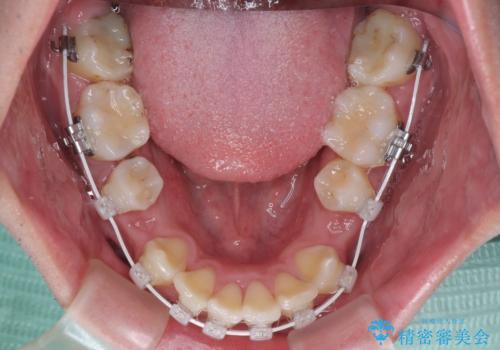

- 審美装置

また、左右ともに最後臼歯が交叉咬合になっており、外側に飛び出している上顎の最後臼歯を補助装置を利用して、積極的に内側に引き込むようにしました。

2年半の治療期間を想定しており、予定通りの期間で無事に終了することができました。